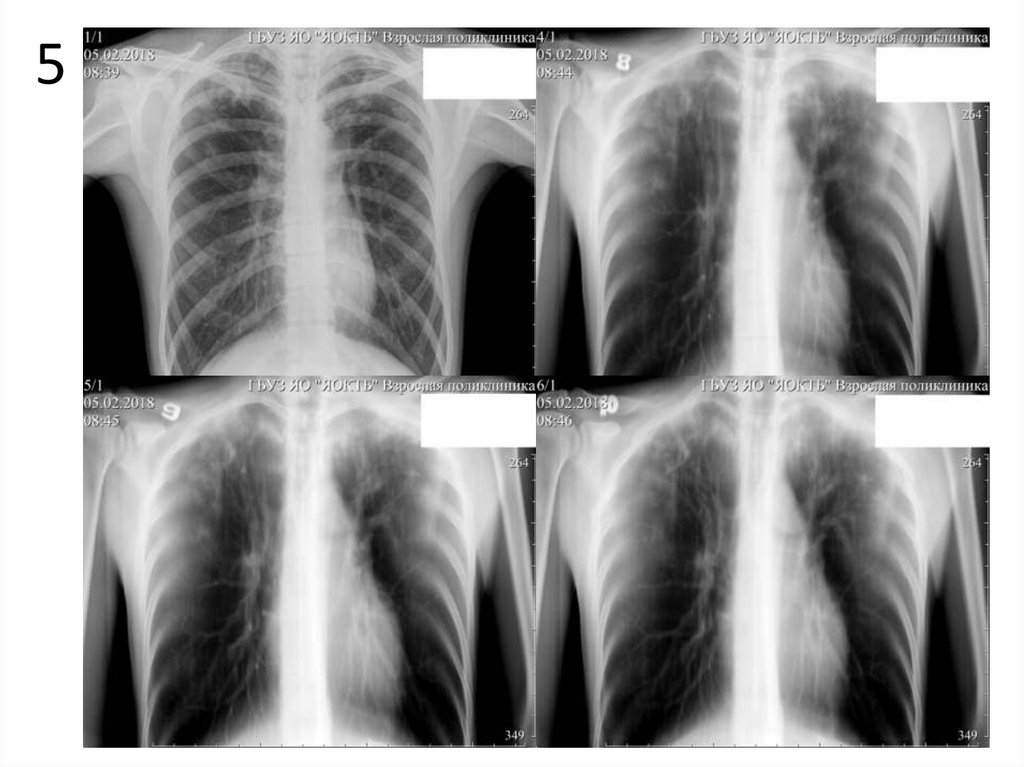

5